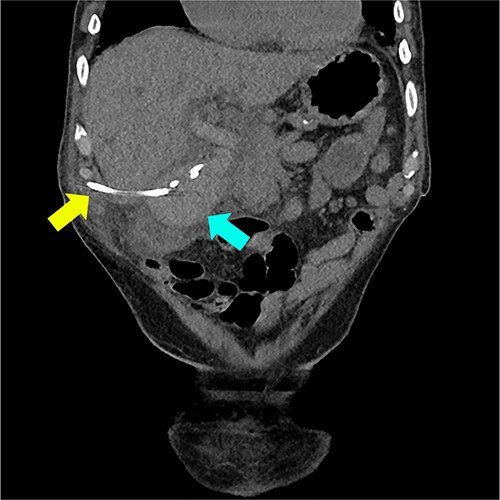

He represented 5 days later with blood draining from the percutaneous cholecystostomy, RUQ pain, and fevers. Two days prior, in the community, international normalised ratio (INR) was 6.2. Bloods on admission included: Hb 118, WCC 23.5, INR 2.4, bilirubin 24/18, ALP 457, GGT 441, ALT 179, and AST 328. CT showed a distended gallbladder with pericholecystic fat stranding and intra- and extrahepatic duct filling defects suggestive of haemobilia (Fig. 3).

Coronal CT reconstruction showing high density material within the lumen of the gallbladder suggestive of haemorrhage (marked with blue arrow) and cholecystostomy tube (marked with yellow arrow).